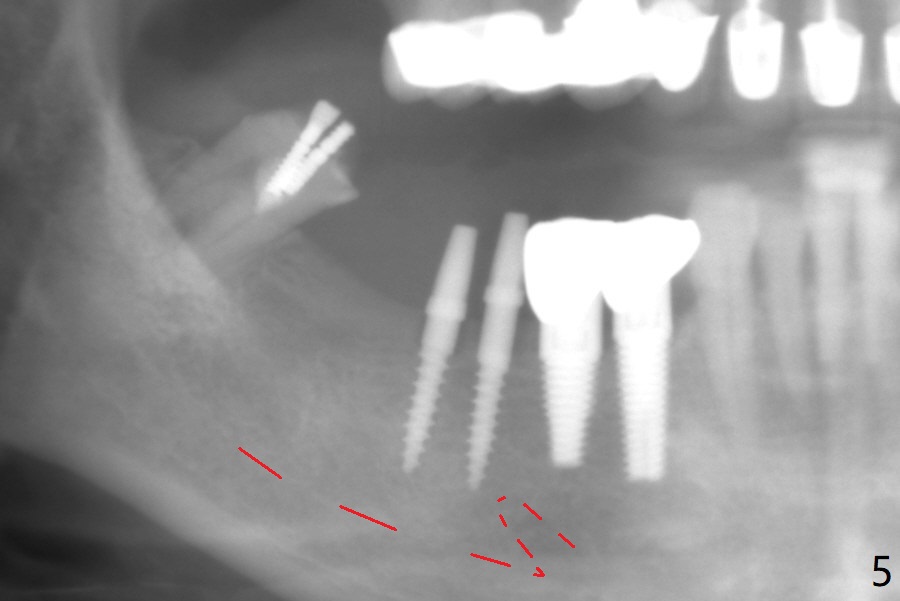

Two of 2.5 mm 1-Piece Implants M

The edentulous ridge at #30 is narrow (Fig.1). After ridge reduction, osteotomy is initiated with 1.2 mm drill for 10 mm; the mesial osteotomy is to be changed (Fig.2 red line). Using a 1.2 mm drill placed in the distal osteotomy (Fig.3 D), the mesial osteotomy changes in trajectory with subsequent placement of a 2.5x10(4) mm 1-piece implant. Since the mesial implant is high in occlusion, the cuff of the distal implant is changed to be 2 mm (Fig.4 (shorter black line)). Panoramic X-ray is taken to show no violation of the Inferior Alveolar Canal (Fig.5 red dashed line). These two 1-piece implants are slightly lingually placed (Fig.6). The crestal bone around the implants resorbs without thread exposure 5 months postop (Fig.7). Impression is taken for a splinted crown (Fig.8-12). There is no metal show around the 2.5 mm 1-piece implants 6 months postop (advantage) vs. that at #28 and 29 (Fig.13). Bitewing is taken post cementation to determine whether residual cement is present (Fig.14). There is periodic swelling and pain in the lower right quadrant 2 years post cementation (Fig.15). In fact periimplantitis appears to have developed at #28 (Fig.16) with loss of the buccal bone (Fig.17,18). The buccal bone loss is less at #29 (Fig.19) and #20 (Fig.23) and no at #30 mesial and distal implants (Fig.20,21). A much smaller implant will be placed lingually at #28 immediate (Fig.24,25).